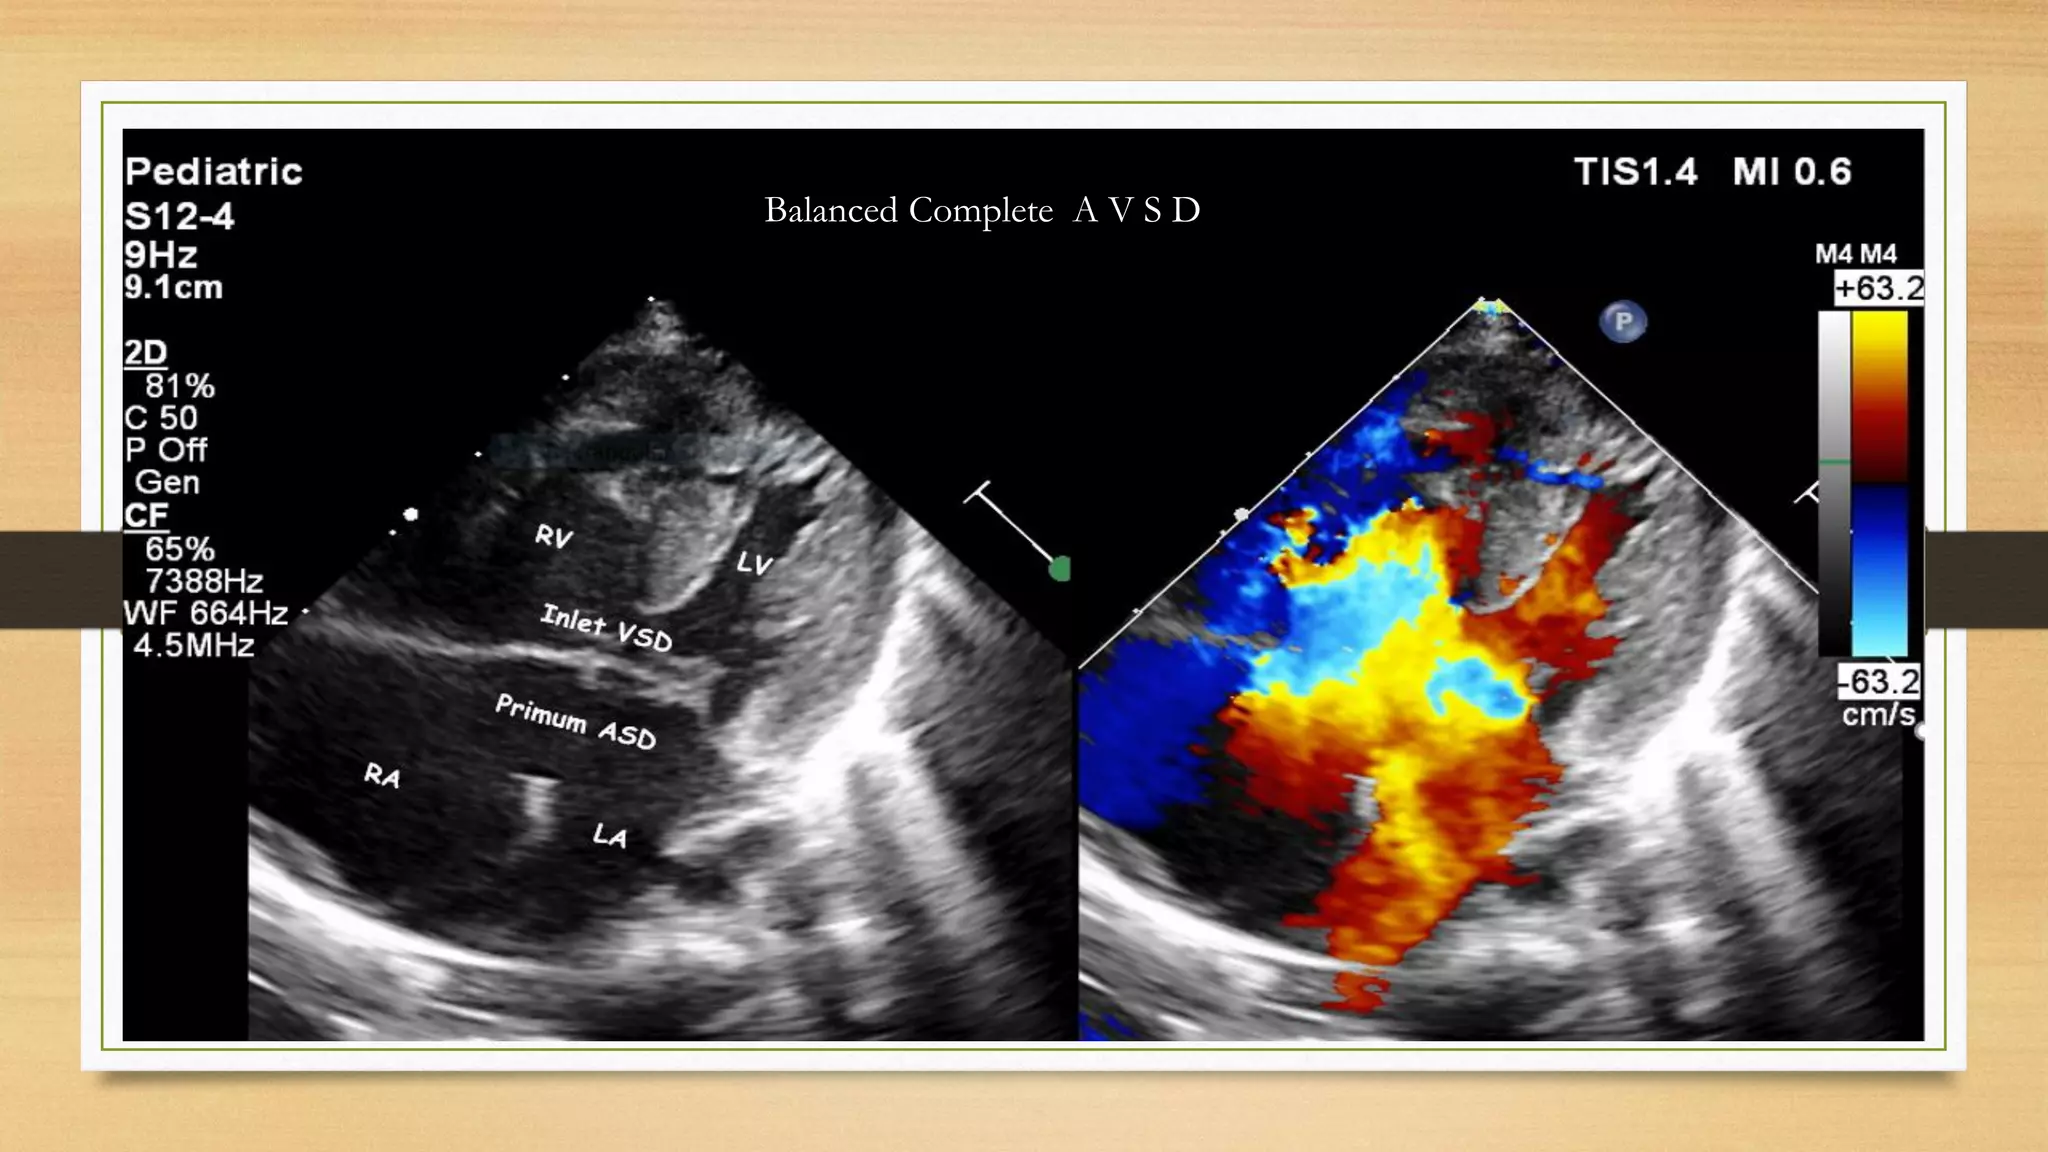

Balanced Complete A V S D

i. Complete AVSD: Large septal defect with an atrial component (ostium primum defect) and a

ventricular component (inlet septal defect), common AV valve ring, and common AV valve.

There may be incompetence of the right- and left-sided parts of the common AV valve.

Complete form of AVSD is generally associated with large left-to-right shunt, pulmonary

artery hypertension, and congestive heart failure. Associated with Down syn, heterotaxy and

Ellis van creveld syn. Anterior displacement of LVOT causes Goose neck deformity- elongated

lvot